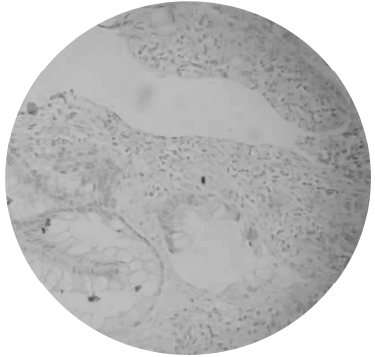

Paciente de 37 anos, transplantado renal por diabetes tipo 1 há 5 anos, vai a consulta ambulatorial com quadro de diarreia aquosa, mais de 10 evacuações ao dia, sem sangue ou muco e febre baixa há 2 meses. Encontra-se em uso de micofenolato mofetil 1 g/dia, tacrolimus 3 mg/dia e prednisona 5 mg/dia. Ao exame físico, encontra-se hidratado e abdômen inocente. Realizou colonoscopia que não evidenciou alterações macroscópicas, porém o resultado de imunohistoquímica em anatomopatológico evidenciou o que é mostrado na figura abaixo.

Enunciado 747615-1

A causa provável da diarreia é